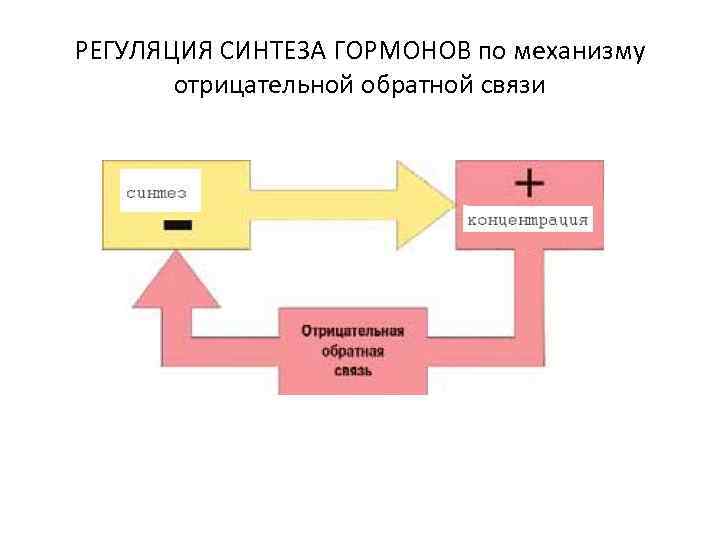

РЕГУЛЯЦИЯ СИНТЕЗА ГОРМОНОВ по механизму отрицательной обратной связи

РЕГУЛЯЦИЯ СИНТЕЗА ГОРМОНОВ по механизму отрицательной обратной связи